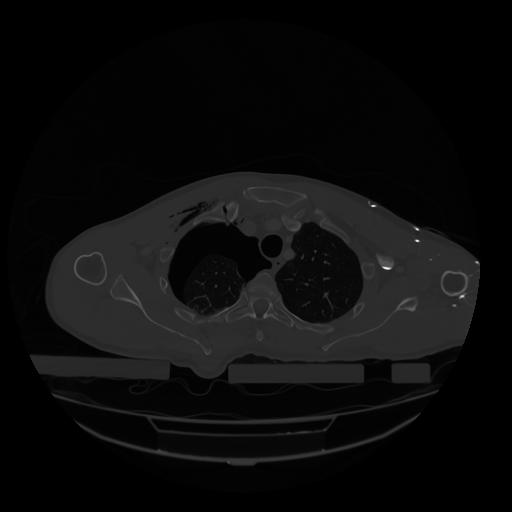

28 CUERPO,CE,Vol,2.0,CUERPO,,